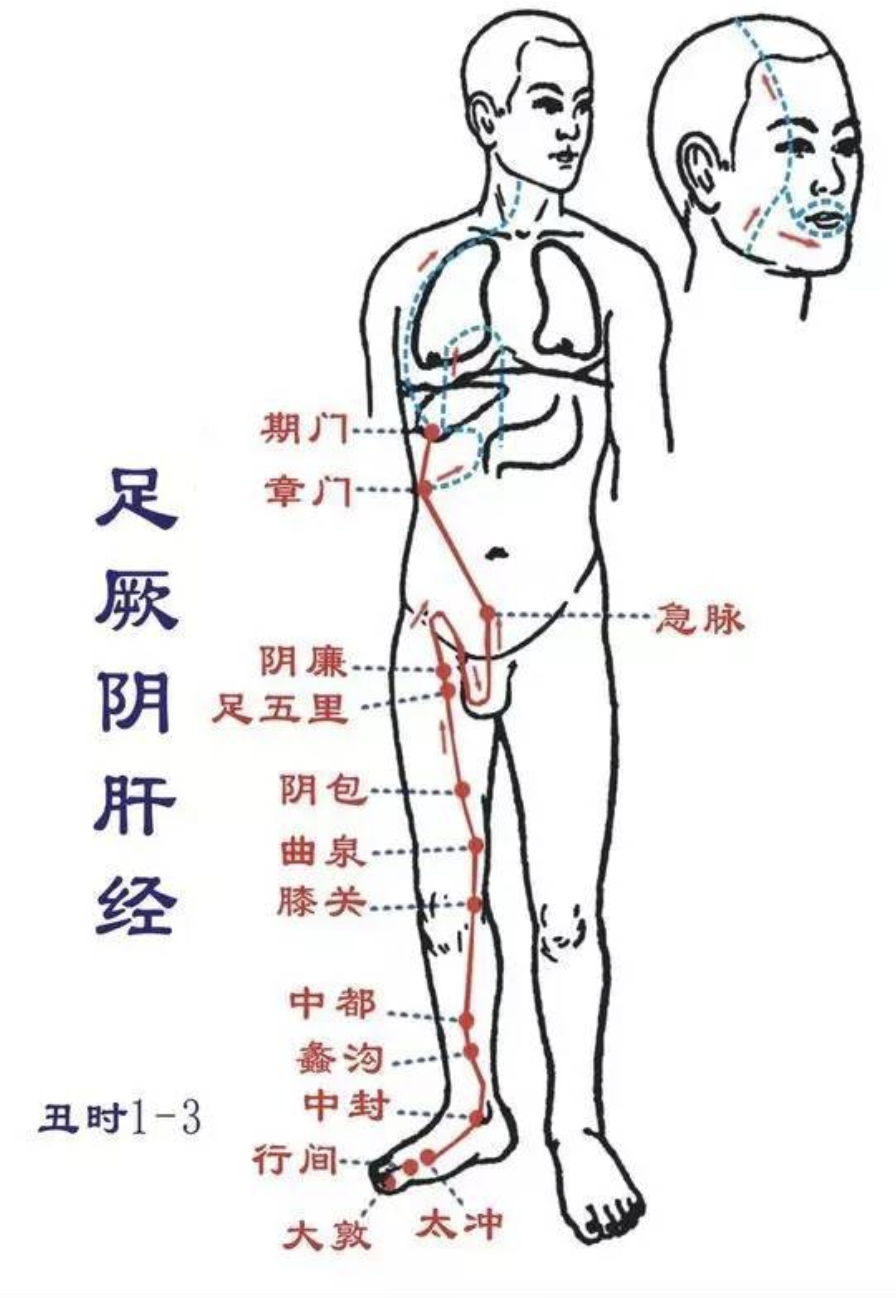

【(十二)足厥阴肝经(图10-30-1)】

1、时辰 丑时 1 ~ 3

2、歌诀 一十四穴足厥阴,大敦行间太冲侵,中封蠡沟中都近,膝关曲泉阴包临,五里阴廉急脉穴,章门常对期门深。

3、经脉循行 起于足大趾上毫毛部(大敦),经内踝前向上至内踝上 8 寸处交出于足太阴经之后,上行沿股内侧,进入阴毛中,绕阴器,上达小腹,夹胃旁,属肝络胆,过膈,分布于胁肋,沿喉咙后面,向上入鼻咽部,连接于“目系”(眼球联系于脑的部位),上出于前额,与督脉汇合于巅顶。

“目系”支脉:下行颊里、环绕唇内。

肝部支脉:从肝分出,过膈,向上流注于肺,与手太阴肺经相接。

4、主要病候 腰痛、胸满、呃逆、遗尿、小便不利、疝气、少腹肿等证。

5、主治概要 主治肝病、妇科、前阴病及经脉循行部位的其他病证。